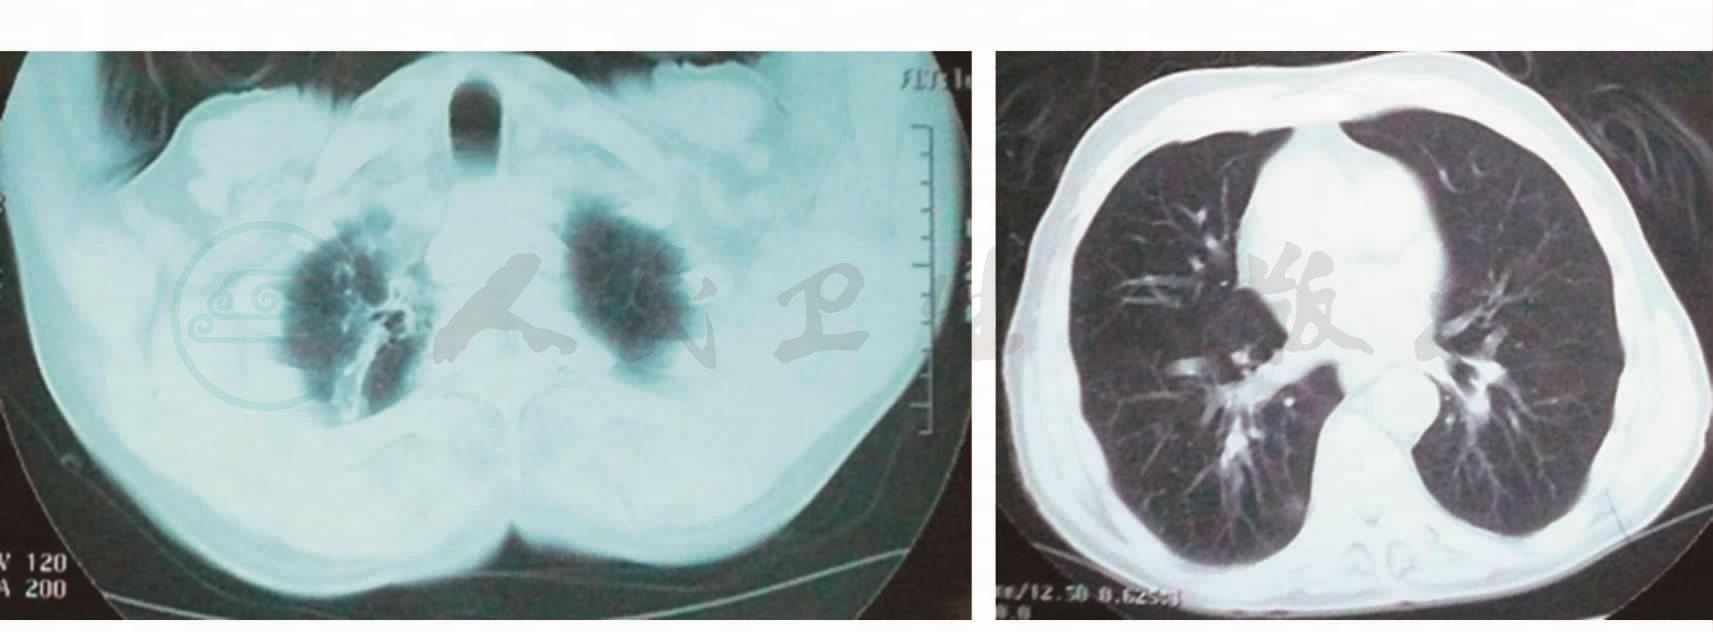

图1 胸部CT(2008-9-24):两肺间质病变,间质炎症;右肺尖索条及牵拉扩张支气管,考虑陈旧性病变;两侧胸膜增厚

诊治经过:患者入院后查血细胞:WBC 4.0×109/L,N 79.1%。血浆Alb:27g/L。血气分析(呼吸空气):PaO2 79.1mmHg,PaCO2 41.2mmHg。考虑为社区获得性肺炎,所以给予左氧氟沙星抗感染治疗。在使用抗生素之前嘱患者清洁口腔后留取痰培养。体温一度正常。于入院后3天患者体温再次升高,达38℃,予对症处理。于入院第5天(左氧氟沙星应用第5天)(复查胸部CT回报:与2008年9月24日胸部CT比较,右肺下叶间质纹理较前增多,右中叶斑片条索影较前局限、浅淡,双肺胸膜下仍见多发磨玻璃影较前增多(图1,图2)。痰培养回报:大肠埃希菌(++++),ESBL(-),多种抗生素敏感。于是我们更换抗生素改为哌拉西林/他唑巴坦抗感染治疗。同日患者四肢、躯干出现红色斑丘疹,不痒,请皮肤科会诊考虑螨虫皮炎,未予特殊处理,数日后皮疹自行消退。入院第15天即哌拉西林/他唑巴坦治疗11天时,患者体温仍无下降趋势,再次复查血常规:WBC 7.97×109/L,N 95.7%。行纤维支气管镜检查并肺活检,镜下所见:大气道结节(图3)。于结节处取活检并行肺活检回报:①(大气道前壁)黏膜慢性炎症,被覆上皮磷化伴不典型增生,间质纤维组织增生;②(右肺下叶)黏膜慢性炎症,并见少许肺组织示间质纤维组织增生;③(刷片)未见肿瘤细胞。这时患者出现喘憋、呼吸困难,PaO2 56.3mmHg。再次复查胸部CT(2008年10 月23日)回报:①右肺膨胀不全伴右侧胸腔积气积液;②左上肺片状密度增高影,考虑感染(图4)。第2次痰培养回报仍为大肠埃希菌(++++),头孢哌酮/舒巴坦敏感,遂更换治疗。复查Alb 23g/L,静脉输注白蛋白纠正低蛋白血症。使用头孢哌酮/舒巴坦治疗5天,体温不见好转。为加强抗感染力度,换用亚胺培南/西司他汀治疗5天,临床症状仍不见好转。其间患者皮疹再次出现,且融合成片,请皮肤科会诊,建议皮肤活检,于肩背部皮肤活检组织回报:表皮内可见中性粒细胞脓肿,真皮浅中层血管周围弥漫炎症浸润,可见中性粒细胞、核尘。这时,我们考虑患者反复发热、抗感染治疗无效,是否同时存在非感染性疾病,于是查免疫全项:IgG 1130mg/ml↑,补体C3 1.3mg/ml↓,CRP 14.6mg/ml↑,类风湿因子1500U/ ml↑,角蛋白抗体(+),抗核抗体(-),抗中性粒细胞胞质抗体(-),请感染免疫科会诊考虑符合类风湿关节炎继发血管炎。于是加用甲泼尼龙40mg,静脉注射,每日一次治疗,2天后体温降至正常,用药7天后改为口服甲泼尼龙治疗,2周后复查胸部CT(2008年11月06日)右侧胸腔积气影消失,胸腔内积液明显减少,两肺上叶磨玻璃影消散(图5),于2008 年11月19日好转出院。住院期间治疗方案与体温变化见图6。